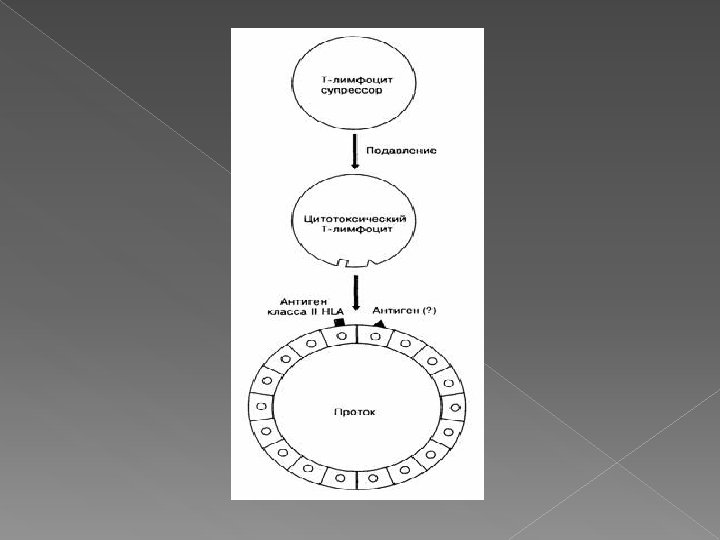

Фотографии и изображения, связанные с симптомами первичного склерозирующего холангита